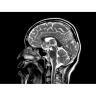

МР-томограф Optima MR450w позволяет получать изображения исключительно высокого качества, которые помогают установить диагноз. Чтобы удовлетворить ожидания клиентов в отношении высокого качества, в МР-томографе Optima MR450w были сохранены дополнительные возможности платформы Discoverу, привнесшие в его работу универсальность и мощь.

• Цифровой РЧ-приемник OpTix — эксклюзивная оптическая РЧ-система увеличивает четкость сигнала и его интенсивность, формируя чистые и резкие изображения.

• РЧ-катушки, оптимизированные для исследования конкретных участков тела — элементы катушек высокой плотности располагаются вокруг исследуемых участков тела и при необходимости обеспечивают расширенный охват и оптимальное качество изображений при каждой процедуре.